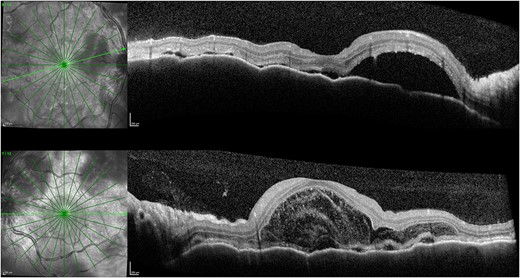

One week after initial review, the patient presented with eye casualty with deteriorated vision of 6/9 in the right eye and count fingers in the left eye. Intraocular pressure was within normal limits in both eyes. Anterior segment examination showed mild anterior uveitis with mild conjunctival injection, 1+ cells in the right eye, 2+ cells in the left eye, and 0.5+ cells in the anterior vitreous of both eyes. No keratic precipitants or posterior synechiae were present in either eye. Fundoscopy revealed bilateral hyperemic discs and 360° choroidal detachments with serous retinal detachment involving the maculae (Fig. 1). There was no evidence of vitritis or retinitis. OCT illustrated detachments of the neurosensory retina and bacillary layers (Fig. 2). Fundus fluorescein angiogram (FFA) demonstrated bilateral disk hyperfluorecence, macular hyperfluorescent pinpoints, and no evidence of retinal vasculitis or ischemia (Fig. 3).

OCT 1 week after initial presentation illustrating neurosensory retinal and bacillary layer detachments, retinal pigment epithelium folds, and darkened choroid pathognomonic for VKH.

OCT 4 months post treatment showed complete resolution of fluid and reinstitution of normal retinal architecture.